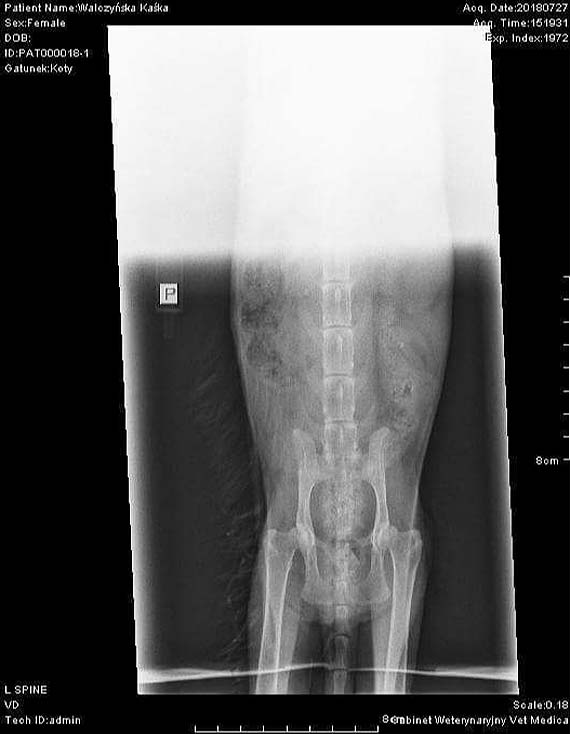

Kotka Kasia nadal oczekuje pomocy

Historia kotki Kasi nie jest taka radosna, jak Wam się wydaje. Kasia nie jest również kotką, która zawsze była wychowywana w ciepłym kącie. już jako mała psotka musiała żyć na wolności dopiero kiedy miała około 3 lat, przekroczyła po raz pierwszy okienko od piwniczki jej opiekunki. I przesiadywała w niej, aż do połowy lipca bieżącego roku. Później droga kotki, runęła i zaczęła mieć problemy zdrowotne. W drugiej połowie lipca, Kasia już nie przybiegła po jedzenie do piwniczki, lecz niestety, przeciągła za sobą z okropnym bólem kończyny.

Ugryziona najprawdopodobniej przez psa Kasia, natychmiast na następny dzień, została przetransportowana do kliniki weterynaryjnej u dr. Kolanków. To właśnie tam, Kasia była po raz pierwszy w życiu u weterynarza. Dostawała zastrzyki oraz tabletki na znieczulenie. Po czasie, została zmieniona lecznica na dr. Karwan-Zimoląg. I to właśnie tam, Kasia leczy się do dnia dzisiejszego. łączna suma wydatków przekroczyła już na pewno ponad 1500 zł. Właśnie dlatego, została założona zrzutka na leczenie kotki.

Na chwilę obecną Kasia, musi zarejestrować się do Kliniki Wrocławskiej na rezonans magnetyczny, aby móc dalej decydować o jej losie. Miłość ma już zapewnioną, lecz niestety prawda finansowa, zawsze zostaje tą prawdą najbardziej bolesną. I wcale to nie jest tak, że my od siebie nic nie dajemy, wręcz przeciwnie próbujemy tyle na ile nas stać. Obecnie kotka jest pod opieką Agnieszki oraz grupy Podziel się ze Mną. Nadal trwa zbiórka pieniężna na wyjazd i dalsze leczenie wraz ze stałymi rehabilitacjami. Istnieje również wydarzenie na FB, na którym prowadzone są licytacje. Pozdrawiamy i liczymy na odzew. Grupa Podziel się ze Mną